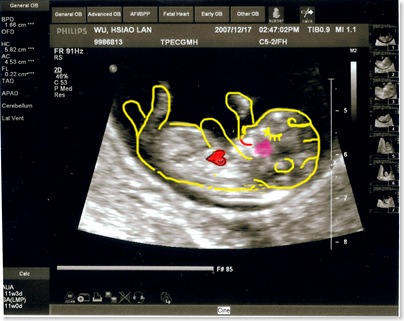

這次的超音波就不用畫圖說故事了吧 !!

再看不懂就只能說.. 你是火星來的嗎

醫生也細心地講解各部位的發育

小baby還一邊揮舞著小手 看起來也像是在吸手指..